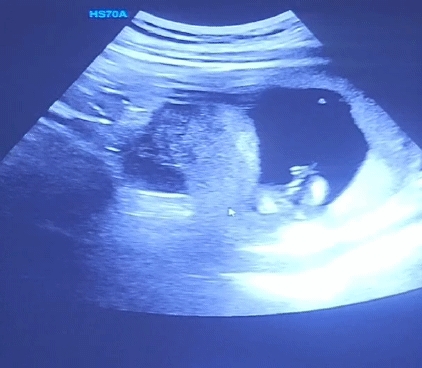

14주 사진이에요! 12주엔 없어보인다고 해주셨는데 오늘은 막 대놓고 보여주지 않네요ㅠ 제눈에만 없어보이는걸까요..

뭘 보시고 있다 없다 하시는 거예요..?ㅜㅜ 형태를 알아볼 수가 없는데..

사진이.... 어디가 어딘지..

다른사진을 올려보심이.. 이거 무슨형태인지 아에 모르겟어요..ㅡㅁㅡㅎ